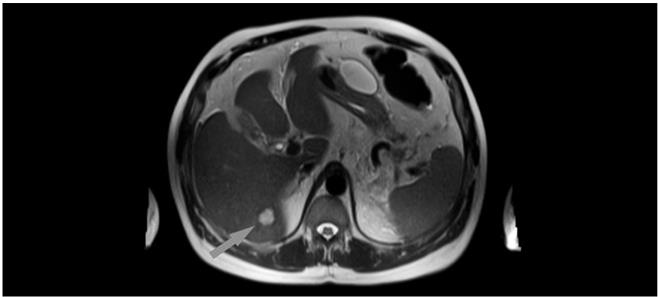

И человек может его получить таким же способом – с немытыми руками, из травы, с растениями с огорода или с пашни, с непромытыми овощами или фруктами, выпив некипяченой воды или просто погладив собаку. И хуже быть ничего не может! Потому что тогда он становится промежуточным хозяином паразита, и его должен съесть волк. Эхинококки выходят из яиц и по уже известной нам дороге – по воротной печеночной вене – попадают из кишечника прямо в печень. И ждут там волка! Именно благодаря печени не происходит заражение паразитами всего организма, печень оставляет их в себе. ![]() Рис. 45. Места обитания эхинококка и расположения кист паразита Эхинококки образуют большущее гнездо с личинками, оно называется эхинококковой кистой печени. В нем есть центральный пузырь с недозревшими личинками и множество внутренних пузырей с более взрослыми личинками. Самое опасное, что может случиться, – это разрыв кисты, который возникает у одного из четырех носителей эхинококка. Это приводит к кровотечению, аллергическому шоку и распространению дочерних кист по всему организму. Да, кисту с личинками эхинококка должен съесть волк. Он их съест, паразиты попадут к нему в кишечник и будут жить долго и счастливо, продолжая выделять яйца во внешнюю среду. Но, как вы понимаете, съесть человека волку сложно. С одной стороны, это хорошо, а с другой – плохо, ведь киста с личинками будет продолжать расти и повреждать печень. Размер таких кист от 10 до 30 см. Немало. Больше просто никто не ждал, киста большего размера начинает сдавливать кровеносные сосуды, артерии, вены, желчные протоки и лимфатические пути, обычно тогда делают обследование и находят этого эхинококка. Кисту с эхинококками, безусловно, удаляют хирурги. Есть и специальные кожные пробы, чтобы определить эхинококка в том случае, если кисты появились в других органах. Обычно сами кисты хорошо видны на УЗИ и лучше всего – на компьютерной томографии, но только с контрастом. Поэтому, если на УЗИ впервые нашли просто кисты, сделайте томографию печени. ![]() Рис. 46. Эхинококковая киста в печени ![]() Некоторым людям как всегда везет, и они получают эхинококк не из травы или воды, как абсолютное большинство промежуточных хозяев, которые ждут волка. Они получают его, когда едят мясо и, мягко говоря, случайно съедают кисту с эхинококком. Ну, наверное, думают, что это деликатес, просто невозможно объяснить это иначе. То есть сами становятся волком, или окончательным хозяином. И их жизнь в полной безопасности, потому что от глиста в кишках они не умрут. Но в смертельной опасности сразу начинают находиться окружающие, ведь получить эхинококк от человека в быту намного легче, чем от животных на природе. Тогда глистов надо травить, возможно, вместе с их хозяином. В таком случае используют курсы противопаразитарных препаратов в соответствии с жизненным циклом паразитов, контролируют анализ кала каждые три месяца в течение года. А родственники судорожно делают УЗИ печени. Будьте осторожны. Печеночный сосальщик Подкласс плоских червей, они же трематоды, они же дигенетические сосальщики, они же двуустки. Самые мелкие и самые плоские и, пожалуй, самые поганые из червей. И имеющие самые красивые названия: фасциола гепатика, описторус фелинеус, шистосома мансони. А этапы жизненного цикла: мирацидий, редий, церкарий, адолескария, марита – песня! Эти паразиты живут в человеке и домашних животных, разные сосальщики паразитируют на разных животных, и практически для каждого из них есть свой сосальщик. Распространены глобально и везде. У нас в стране больше печеночного и кошачьего сосальщика, или описторха. ![]() Рис. 47. Внешний вид печеночного сосальщика Сосальщики откладывают яйца, которые выходят из кишечника во внешнюю среду. Друзья, когда будете на улице, не трогайте улиток, а если купаетесь, не берите ракушки. Именно в них попадают вышедшие из яиц личинки с красивым названием мирацидий. Печеночный сосальщик предпочитает обычную улитку прудовика, описторхи любят других наших обычных улиток битиний. В этих ракушках личинки дозревают в течение пары месяцев и превращаются в хвостатых церкарий, они заражают животных или рыбу, а шистосомы обходятся без них и сразу проникают через кожу человека. ![]() Рис. 48. Жизненный цикл сосальщика Получить такого прекрасного сосальщика можно либо с водой, травой, либо с плохо помытыми овощами. Еще можно получить его, часто общаясь с улитками или купаясь в загрязненных водоемах. И летний запрет на купание в отдельных местах – это не всегда и не только кишечная палочка! Будьте осторожны. Отдельного внимания заслуживает сырая рыба, которая может быть нашпигована не только аскаридами и широким лентецом, но и кошачьей двуусткой, или описторхом. В нашей стране особенно это касается районов сибирских рек, в которых добывают много промысловой рыбы. Описторх предпочитает семейство карповых рыб, но не брезгует и другими. Заражение происходит личинками, которые активизируются в кишечнике и по все той же замечательной дороге в печень приходят к ее воротам по воротной печеночной вене. Паразиты проникают в печень, проедают в ней ходы и через пару месяцев поселяются в желчных протоках. Печеночного сосальщика можно разглядеть только если он отстыкуется от печени. Размер его около 2 см в длину и 1 мм в толщину, он похож на маленький листочек, а не на кусочек неба. Имеет две мощные присоски и двойной кишечник. Питается кровью и клетками печени. Описторхи поменьше и потолще, около 1 см в длину и 2 мм в толщину. И тоже с двумя присосками. Сосальщики могут быть одиноки, в том смысле, что им не нужен второй червяк для размножения, как аскаридам. У этих все с собой: они двуполые – полный комплект! Еще и долгожители, в среднем могут сосать кровь и поедать печень от 5 до 20 лет! |